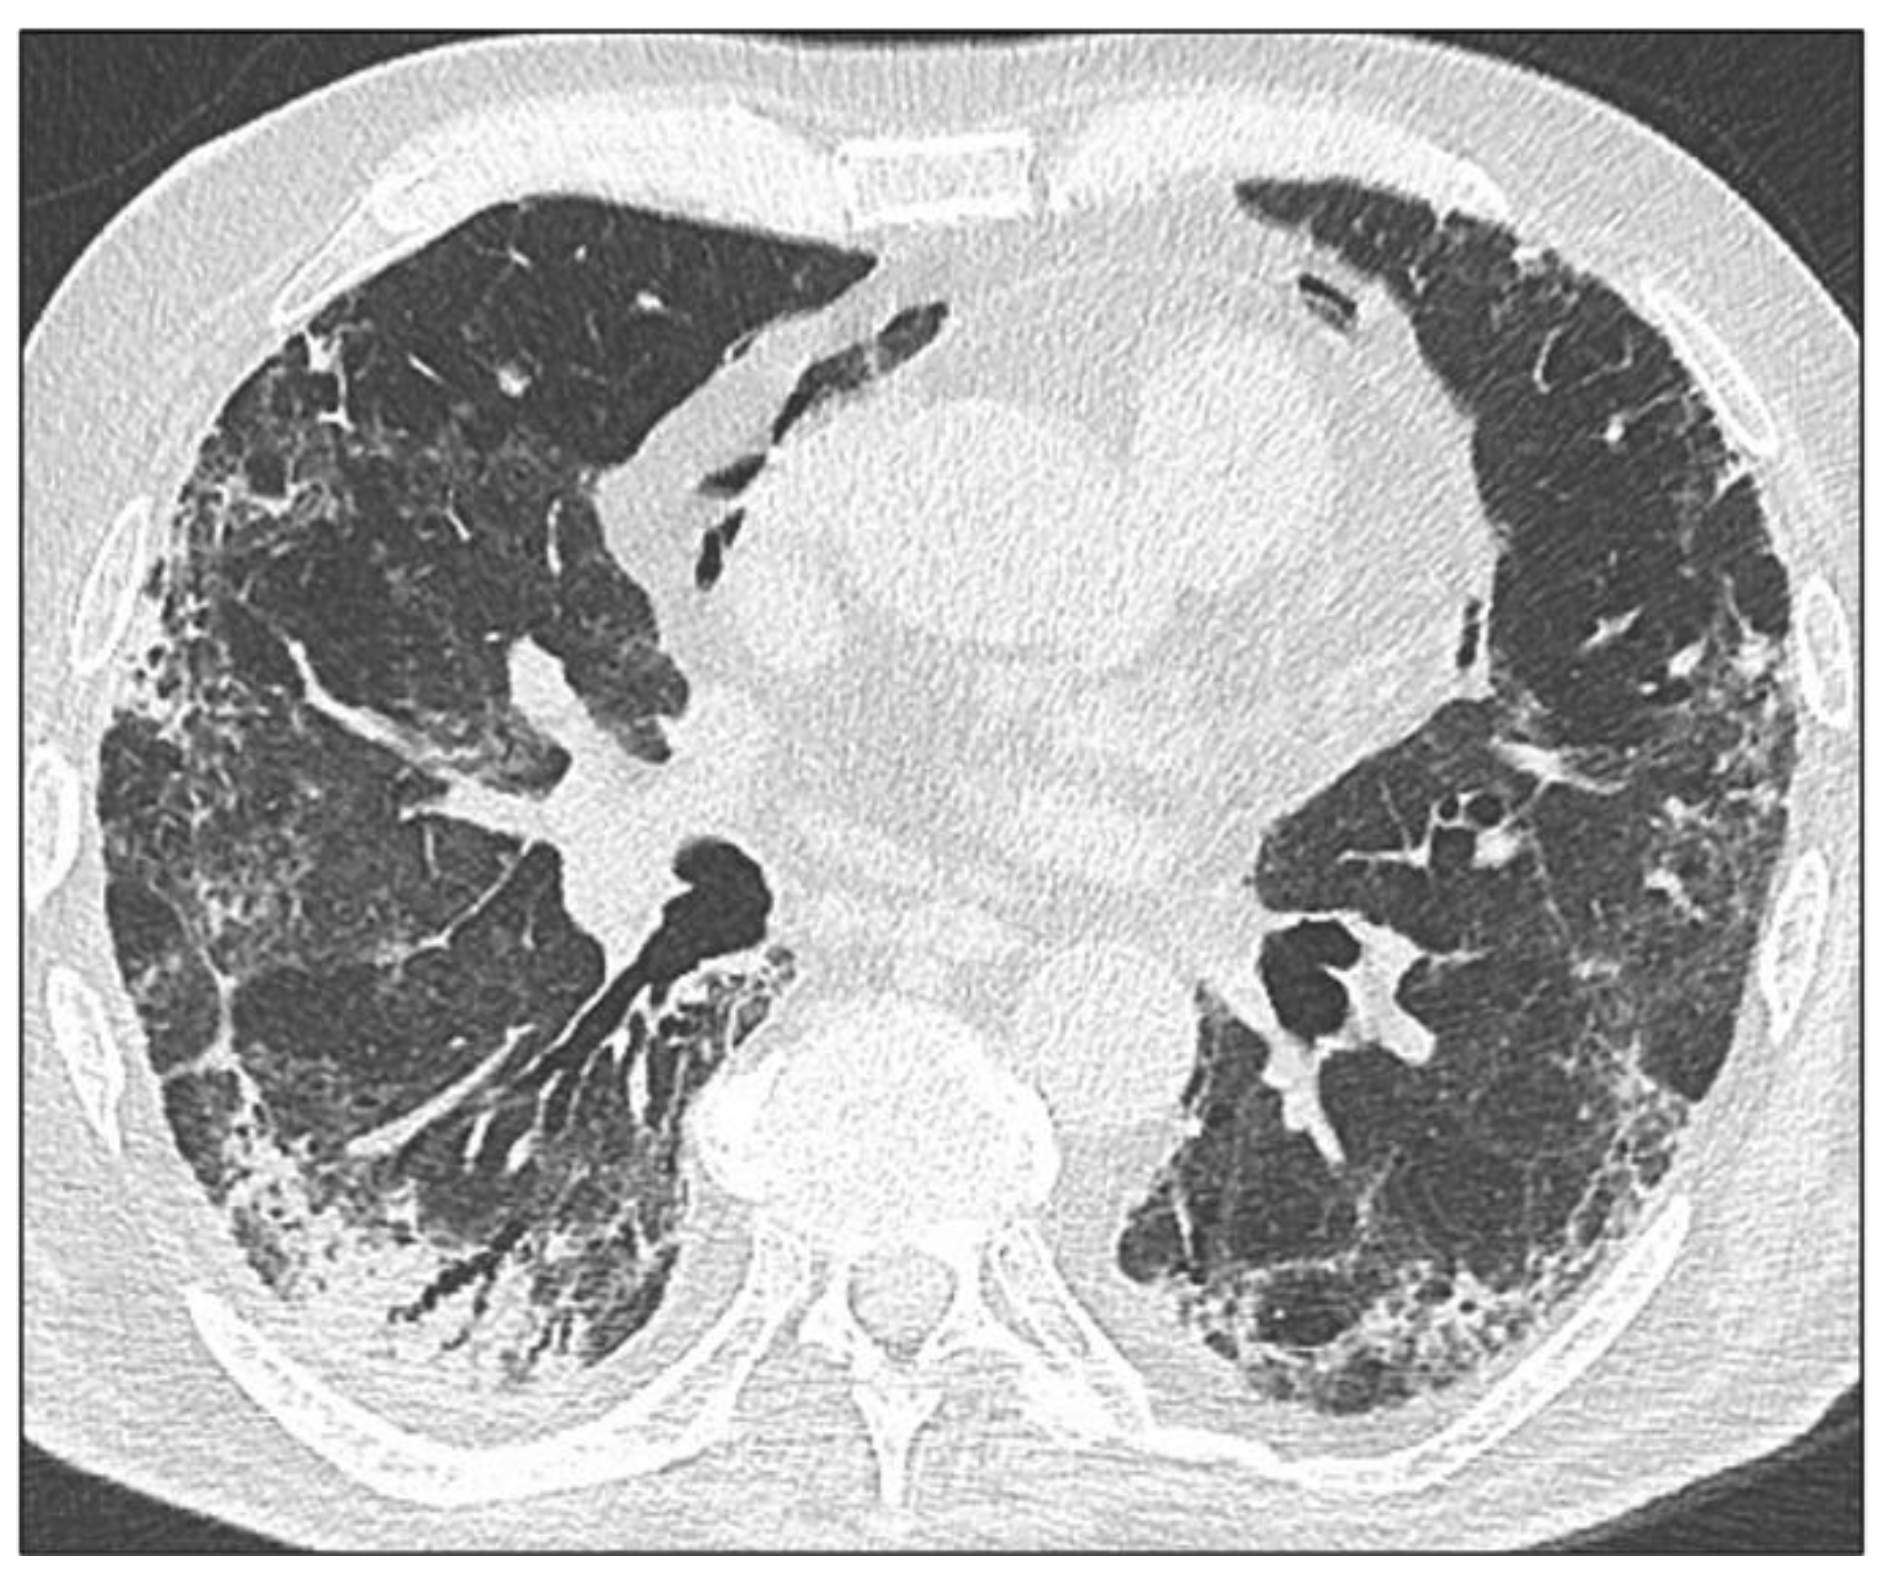

3.1. HRCT Imaging Findings

3.1.1. Ground Glass Opacities